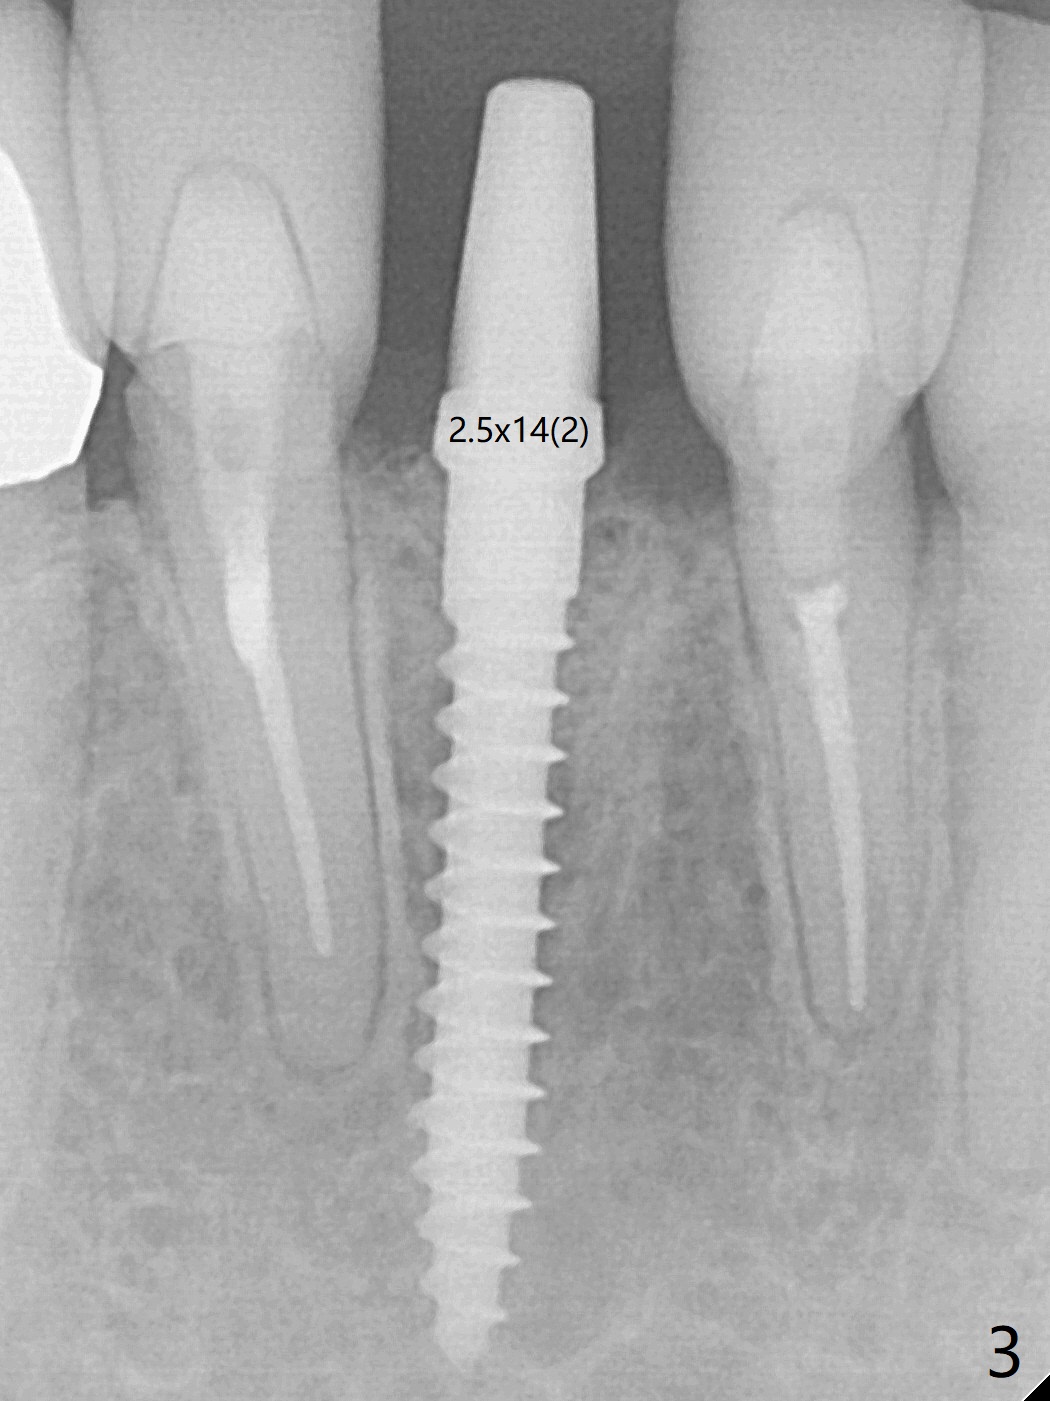

A drawback of implant planning at #25 is not to use a preop PA (Fig.1 (^ fracture line)). The initial trajectory seems to be alright (Fig.2), but a 2.5x14(2) mm implant placed is close to the tooth #26 (Fig.3). In fact the affected tooth is deviated distal; osteotomy should be initiated in the mesial slope of the socket (Fig.4 red line). The final trajectory appears to be perfect (Fig.5). Furthermore the 1st intraop PA should be analyzed carefully (Fig.6). A new osteotomy should be established mesial or the existing one should be moved mesial with Lindamann bur (Fig.7). The distal implant placement may be related to more bone loss in the distal crest 3.5 months postop (Fig.8) and more severe distal papillary recession (Fig.9 *). The bone density increases at the levels of the non-thread and thread portions of the implant (in the original socket) nearly 10 months post cementation (Fig.11 *, <). There is no bone loss 16 months post cementation (Fig.12).